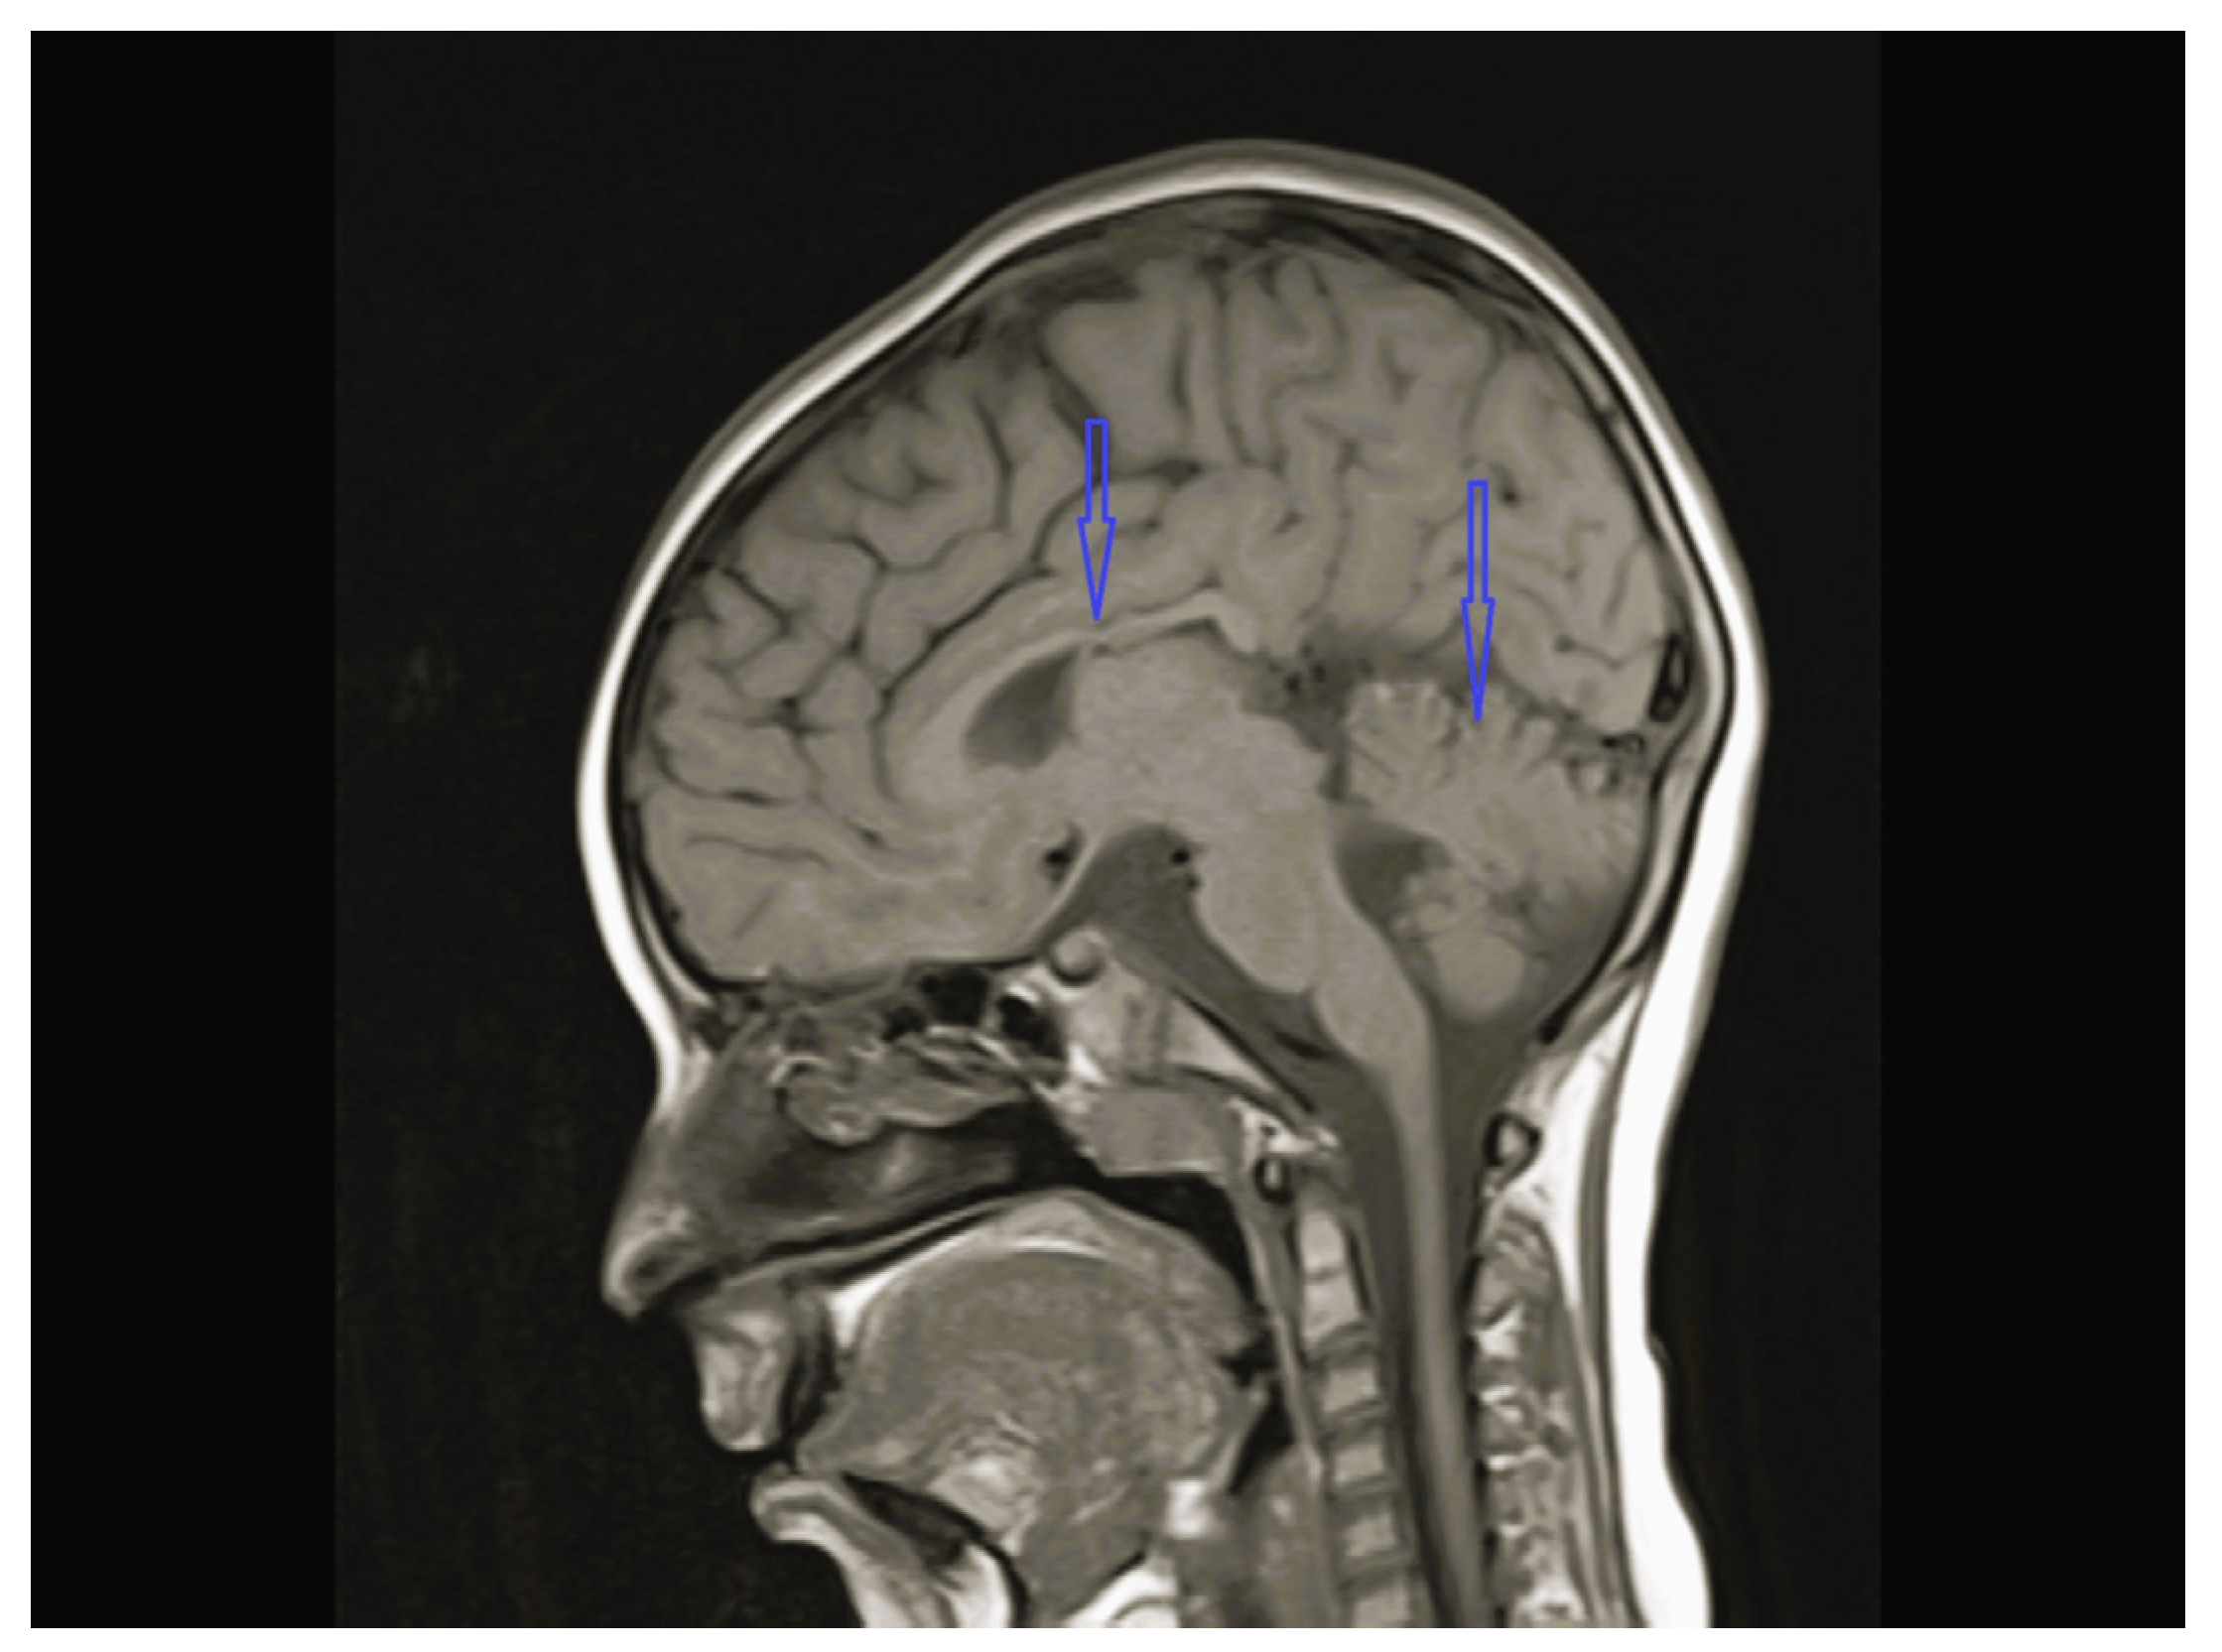

| 3 | Normal | - | Normal | Vermis and CC hypoplasia | Normal | KIF1A c.773C>T heterozygote (p.V391M) | Physical therapy, baclofen |

| 8 | Normal | - | Multifocal spike and waves pattern | Vermian, CC and brainstem hypoplasia | Normal | KIDINS220 NM_020738.4 c.4388C>A heterozygote p.S1463* | Physical therapy, clonazepam, sodium valproate |